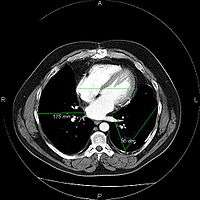

The same image following contrast adjustment, sharpening and measurement tags added by the system